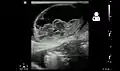

Ultrasound showing an incarcerated umbilical hernia[9]